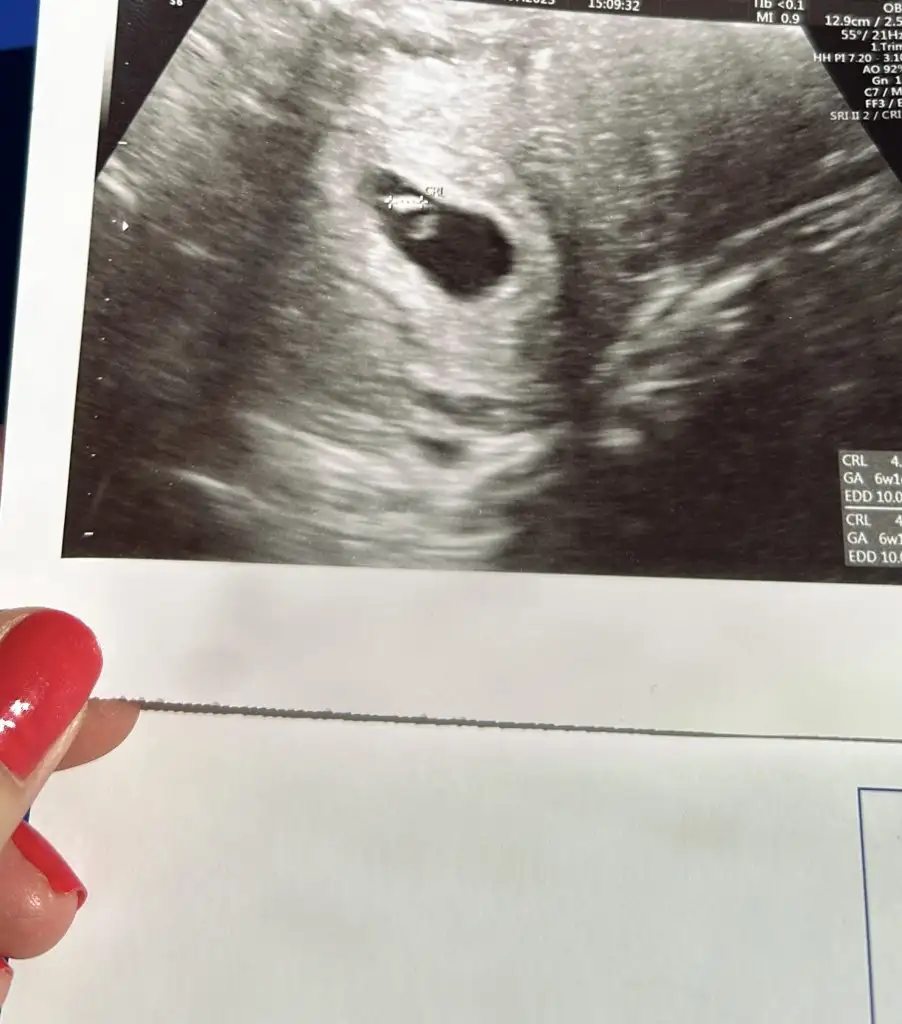

Merhaba ben 5+1 de keseyi gördüm 6mm idi çok minik yolk kesesi vardı nokta kadar, ama belki 1 gün önce gitsem gözükmezdi bence bi kaç gün bekleyin üzülmeyin geç döllenme muhtemelen, karından mı baktı vajinal mi?Kızlar merhaba. Bugün yine doktora gittim 5+3 kese görünüyor ama bebeği göremedi. Boş gebelik olabilir dedi. Çok korkuyorum. Kese 6mm büyüklükte. Sizlerin bu dönemlerde nasıldı. Yolk kesesini ne zaman gördünüz?

Karından baktıMerhaba ben 5+1 de keseyi gördüm 6mm idi çok minik yolk kesesi vardı nokta kadar, ama belki 1 gün önce gitsem gözükmezdi bence bi kaç gün bekleyin üzülmeyin geç döllenme muhtemelen, karından mı baktı vajinal mi?

Cnm bnde doktordan gelıyorum şimdiKızlar merhaba. Bugün yine doktora gittim 5+3 kese görünüyor ama bebeği göremedi. Boş gebelik olabilir dedi. Çok korkuyorum. Kese 6mm büyüklükte. Sizlerin bu dönemlerde nasıldı. Yolk kesesini ne zaman gördünüz?

Bnde bugun 5+4 üm

Karından keseyi gördü

Kese 5 mm dedi

Ben bugün gittim 4+6 keseyi zar zor gördü. Bu kadar erken bebek görünmez ki hem de değer geç döllenme gibi. Bebek 6. Haftadan sonra görünüyor genelde karından ultrason ile. Hatta ben oğlumu 8. Haftada gördümKızlar merhaba. Bugün yine doktora gittim 5+3 kese görünüyor ama bebeği göremedi. Boş gebelik olabilir dedi. Çok korkuyorum. Kese 6mm büyüklükte. Sizlerin bu dönemlerde nasıldı. Yolk kesesini ne zaman gördünüz?